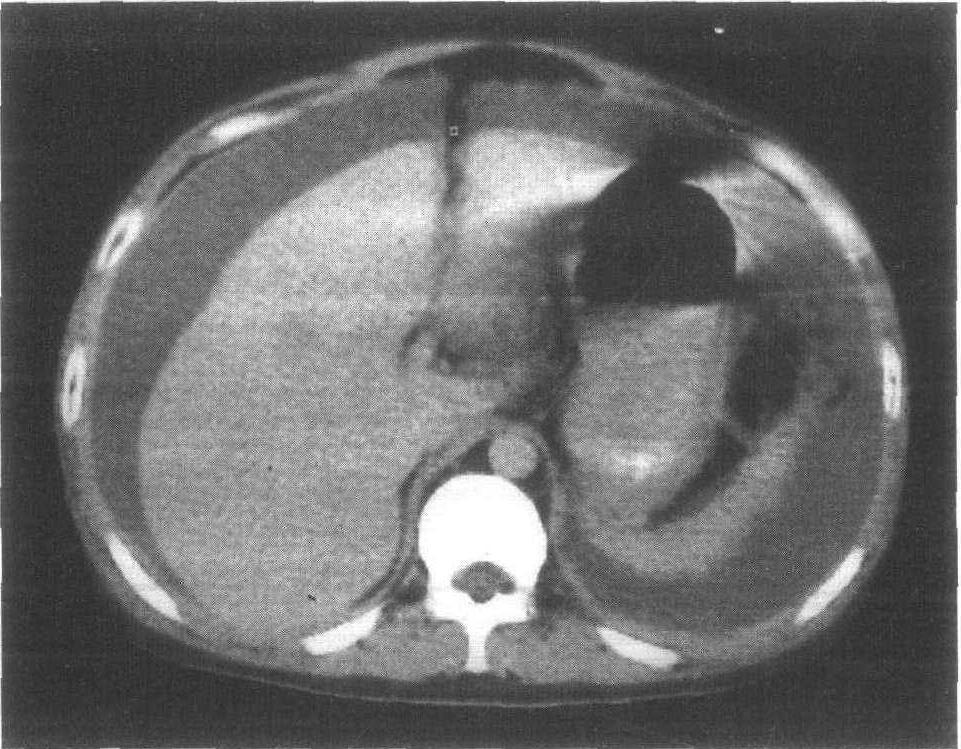

胃肠穿孔可造成腹腔积气 。 腹腔或盆腔肿块(如卵巢囊肿、肝肿瘤)以及肿大的脏器(如脾肿大、肝肿大等)均可使腹内压力增加 , 引起腹胀 。